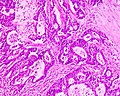

Medullary carcinoma of cecum of elderly woman. A. Tumor extends from the luminal surface at upper left into the muscularis propria at lower right. Note variable longitudinal spaces in the tumor. B. Tumor extends into pericolic fat. Note relative circumscription, with pushing borders. C. Tumor cells, often in seeming syncitiums, strew lymphocytes. D. In other areas, there appears to be a pattern suggesting nests and stromal trabeculums. Chromogranin/synaptophysin were negative.